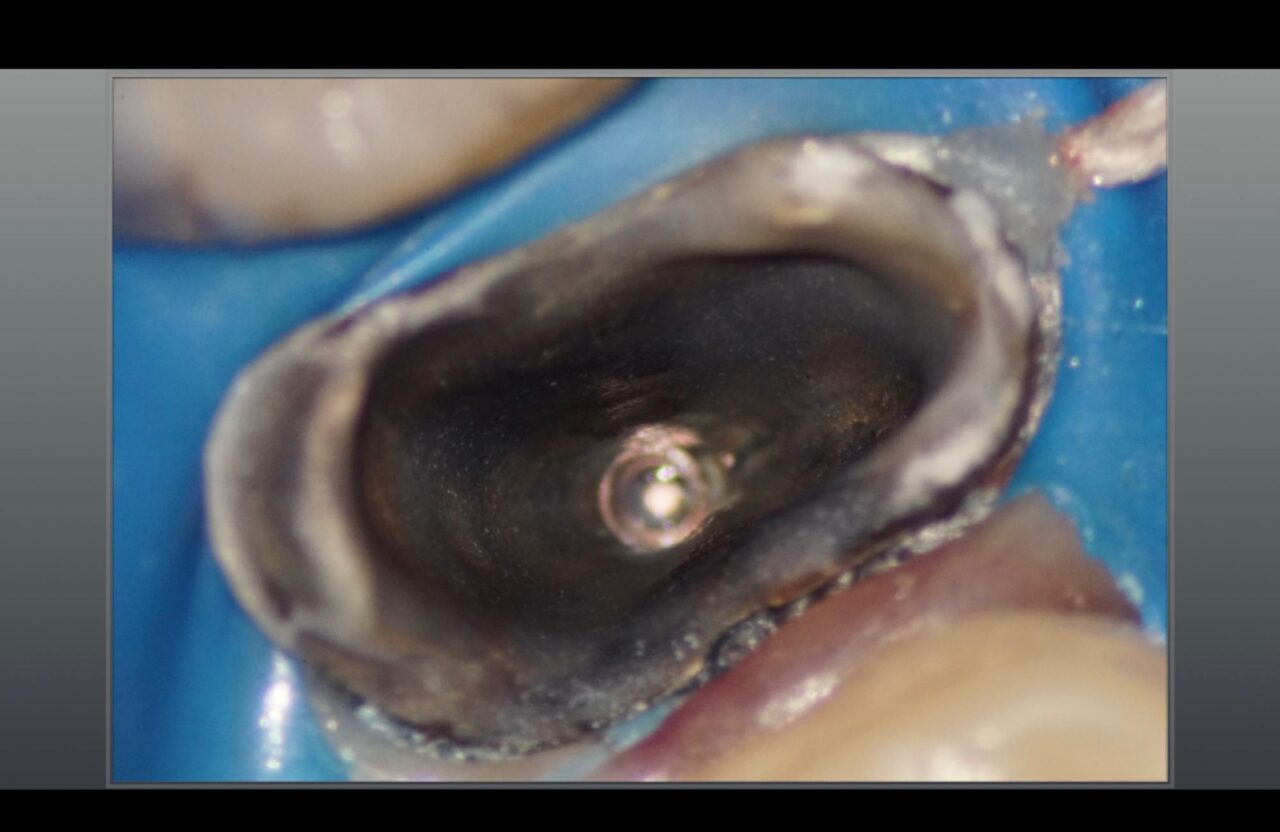

腐った歯の症例1

感染根管治療のため麻酔を行い、ラバーダム防湿を通法道理に行った。そして善意が治療した冠を外すと、見ての通り腐食している状態になっている。

次に金属の土台、メタルポストが入っているので、余計な歯質を削らないように外した。

次に根管内の感染部を除去して、前医が根管充填したガッタパーチャを除去した。

可能な限り変色している歯質は、除去したのですが、削りすぎると歯の強度が弱くなってしまうので慎重にう蝕検知液を用いながら削って行った。

根管内を削って行くと、垂直性の破折線を確認した。

標準的な診断機基準ではこの写真が取れると根管治療が終了で、抜歯となる。しかし吉松歯科医院では垂直性の破折でも可能な限り接着技術を用いて歯の保存をしている。

破折線に接着剤を流し込んだ写真。